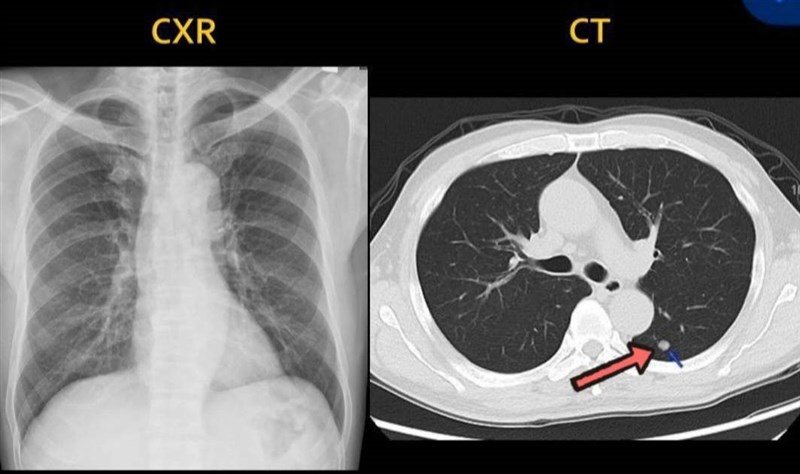

張男的X光檢查沒有異狀,但是電腦斷層卻有肺結節。圖/阮綜合醫院提供

【記者王淑芬高雄報導】57歲的張男健檢X光檢查沒有異常,但透過電腦斷層篩檢發現左肺有肺結節。73歲的阿嬤大腸鏡檢查正常,但血液癌症指數卻標也經電腦斷層發現右肺葉有2顆腫瘤。醫生建議早期肺癌藉低劑量電腦斷層診斷及追蹤有助於提高治癒率。

阮綜合醫院胸腔外科醫師戴碩瑩今天指出,張男於門診就醫自訴有40年菸齡,偶有輕微胸痛。就醫透過X光檢查沒有異常,後來再以電腦斷層檢查發現左肺有0.7公分肺結節,於是醫院為張男以傷口小、預後快的「單孔胸腔鏡」微創手術做治療,所幸病理檢查結果為良性肺結節,終於讓張男意識到健康的重要,開始戒菸了。

醫師表示,十大死因中,惡性腫瘤居首位,而肺癌又是十大癌症死亡人數的第一名。醫師鼓勵民眾做健檢,只是腫瘤大到1分以上才會被X光偵測到,低劑量電腦斷層可以偵測3至4mm大小的肺結節。

戴碩瑩說,肺癌初始症狀不明顯,胸部X光檢驗不易偵測,建議早期肺癌藉助低劑量電腦斷層診斷及追蹤。45歲以上民眾如屬於高風險族群者盡早作篩檢,能提高治癒及存活率。